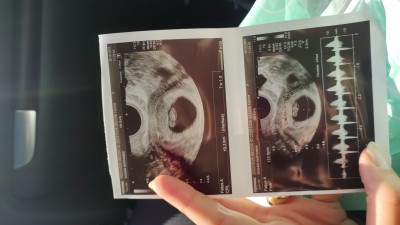

Tam 6+6 da kalp atışını duyduk. Ultrason resmini ekliyorum.  Cinsiyet tahmini yapan arkadaşlarim var sizce bu kadarcikken belli oluyor mu keseye göre.

Gebelik haftası 7